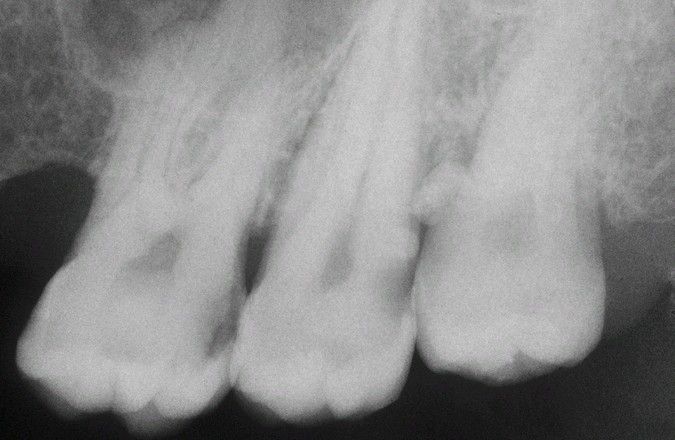

Enamel pearl radiograph

Radiopaque nodule on the mesial surface of the root of the maxillary third molar. Another less distinct enamel pearl is present on the distal root of the second molar.